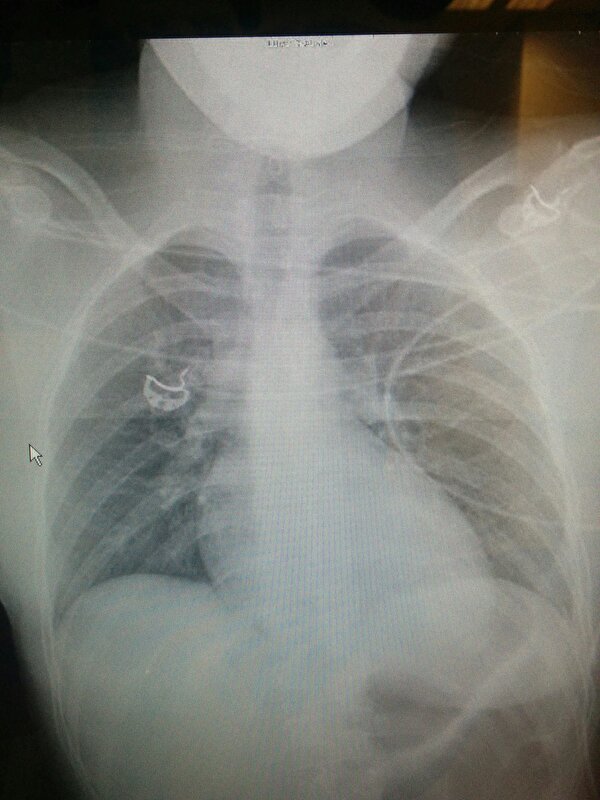

6 gebroken ribben links,

Klaplong en gescheurde milt die gelukkig tot nu toe zo stabiel is en gestopt is met bloeden dat daar nu nog geen operatie voor nodig is.

Flink pijn mijn ruggengraat, Helaas teveel vocht en is dat lastig te beoordelen, voor zover ze dat kunnen zien lijkt die gelukkig heel te zijn